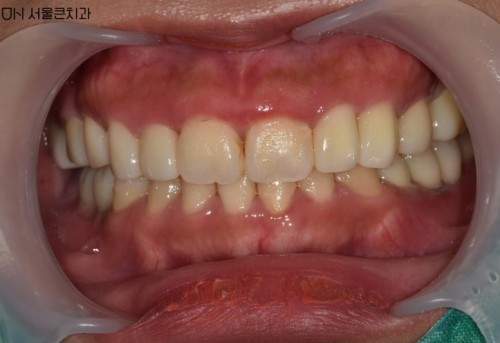

6 60대 남환 임플란트

• 위아래 틀니쓰시는 분으로 위아래 전체 임플란트를 원하시는..